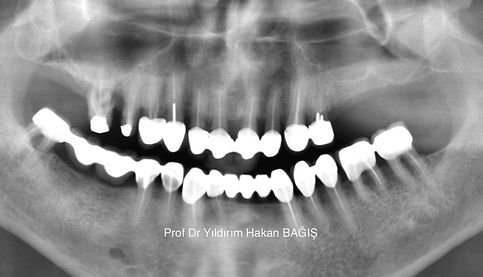

PROF DR YILDIRIM HAKAN BAĞIŞ